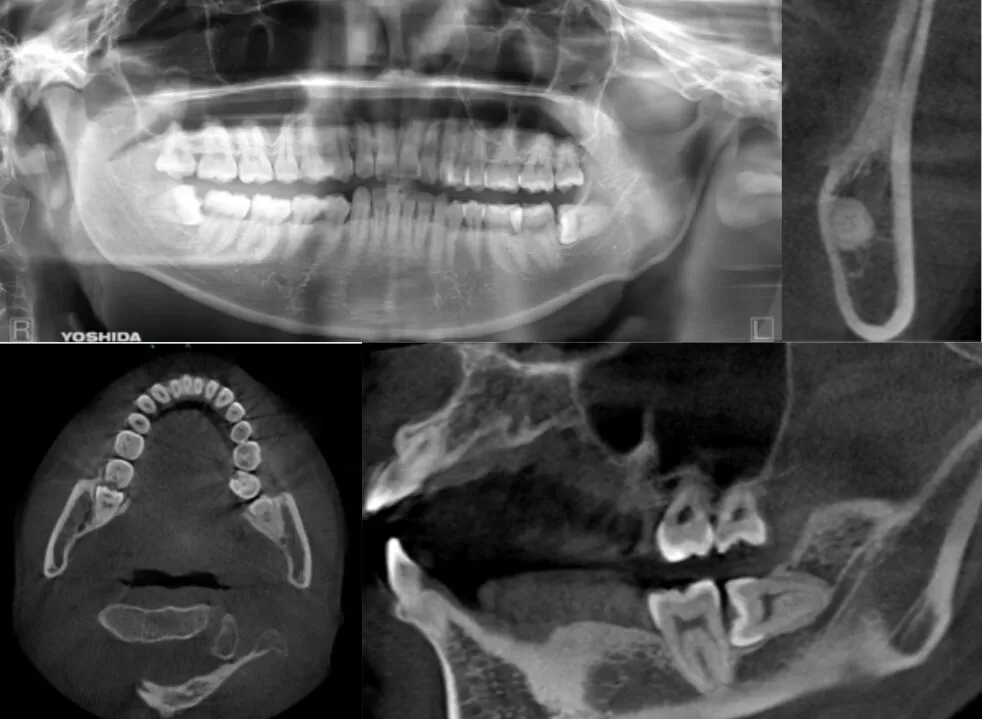

冠状断にて1根 矢状断にて最大豊隆部下方まで下顎枝が被覆している症例

| 患者情報 | 27歳 男性 |

| 手術時間 | 10分 |

| 治療内容 | 親知らず抜歯 |

| グレゴリー分類 | クラスⅠ position B |